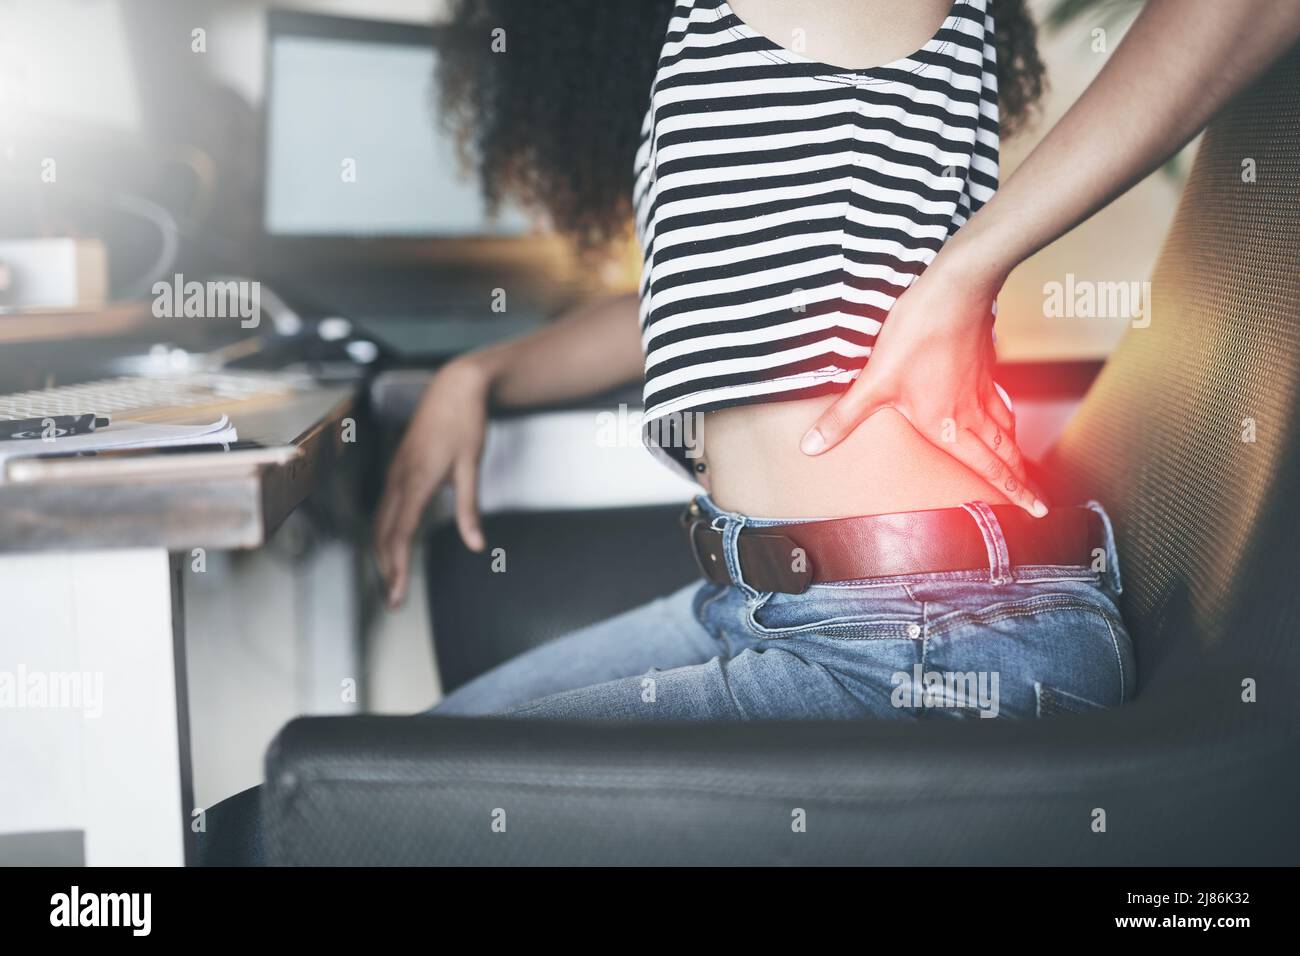

C'est que mon nerf sciatique flip à nouveau Banque D'Imageshttps://www.alamyimages.fr/image-license-details/?v=1https://www.alamyimages.fr/c-est-que-mon-nerf-sciatique-flip-a-nouveau-image469743878.html

C'est que mon nerf sciatique flip à nouveau Banque D'Imageshttps://www.alamyimages.fr/image-license-details/?v=1https://www.alamyimages.fr/c-est-que-mon-nerf-sciatique-flip-a-nouveau-image469743878.htmlRF2J86K32–C'est que mon nerf sciatique flip à nouveau